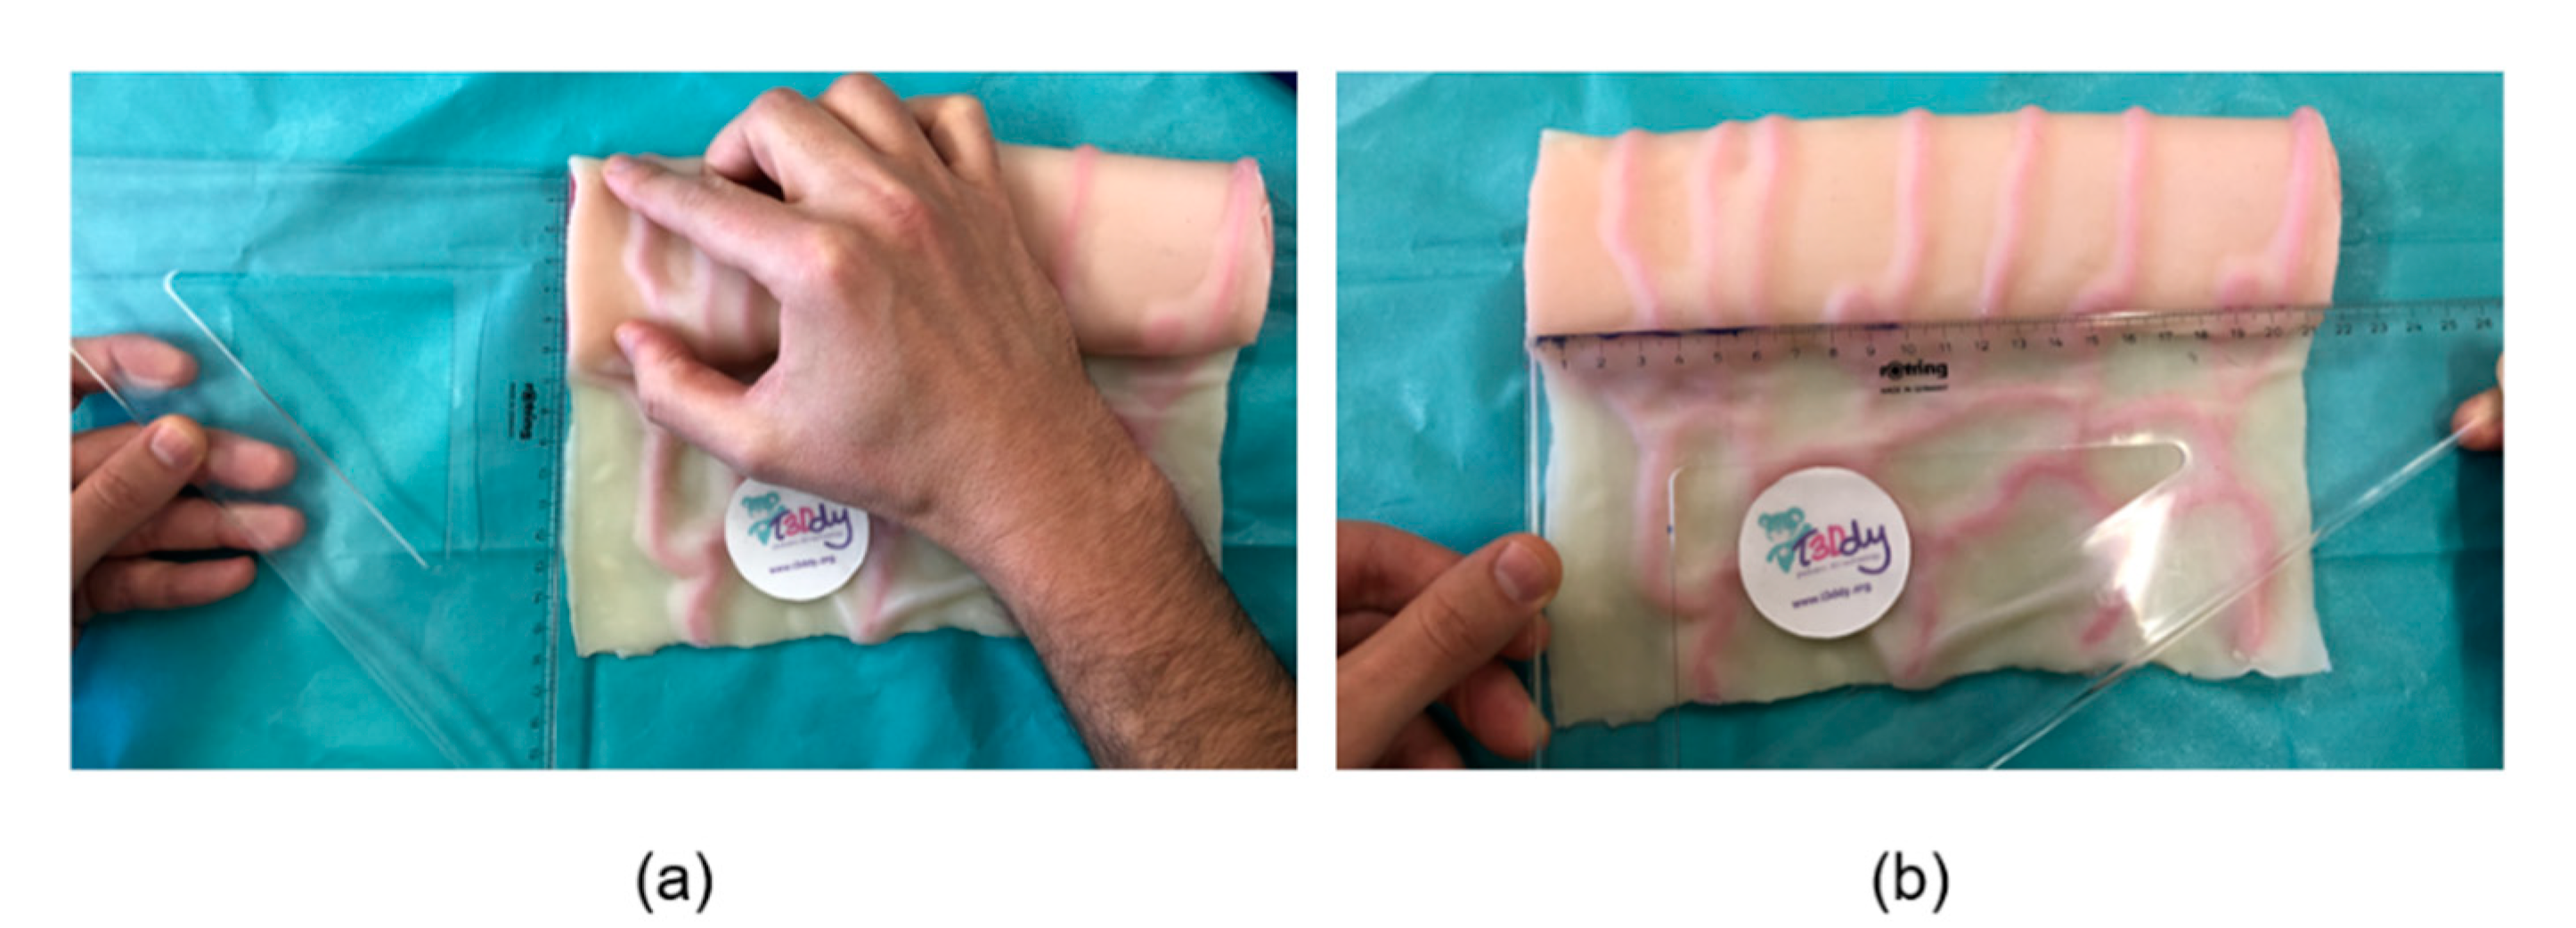

2. Materials and Methods

2.1. The Geometry of the SILT Procedure